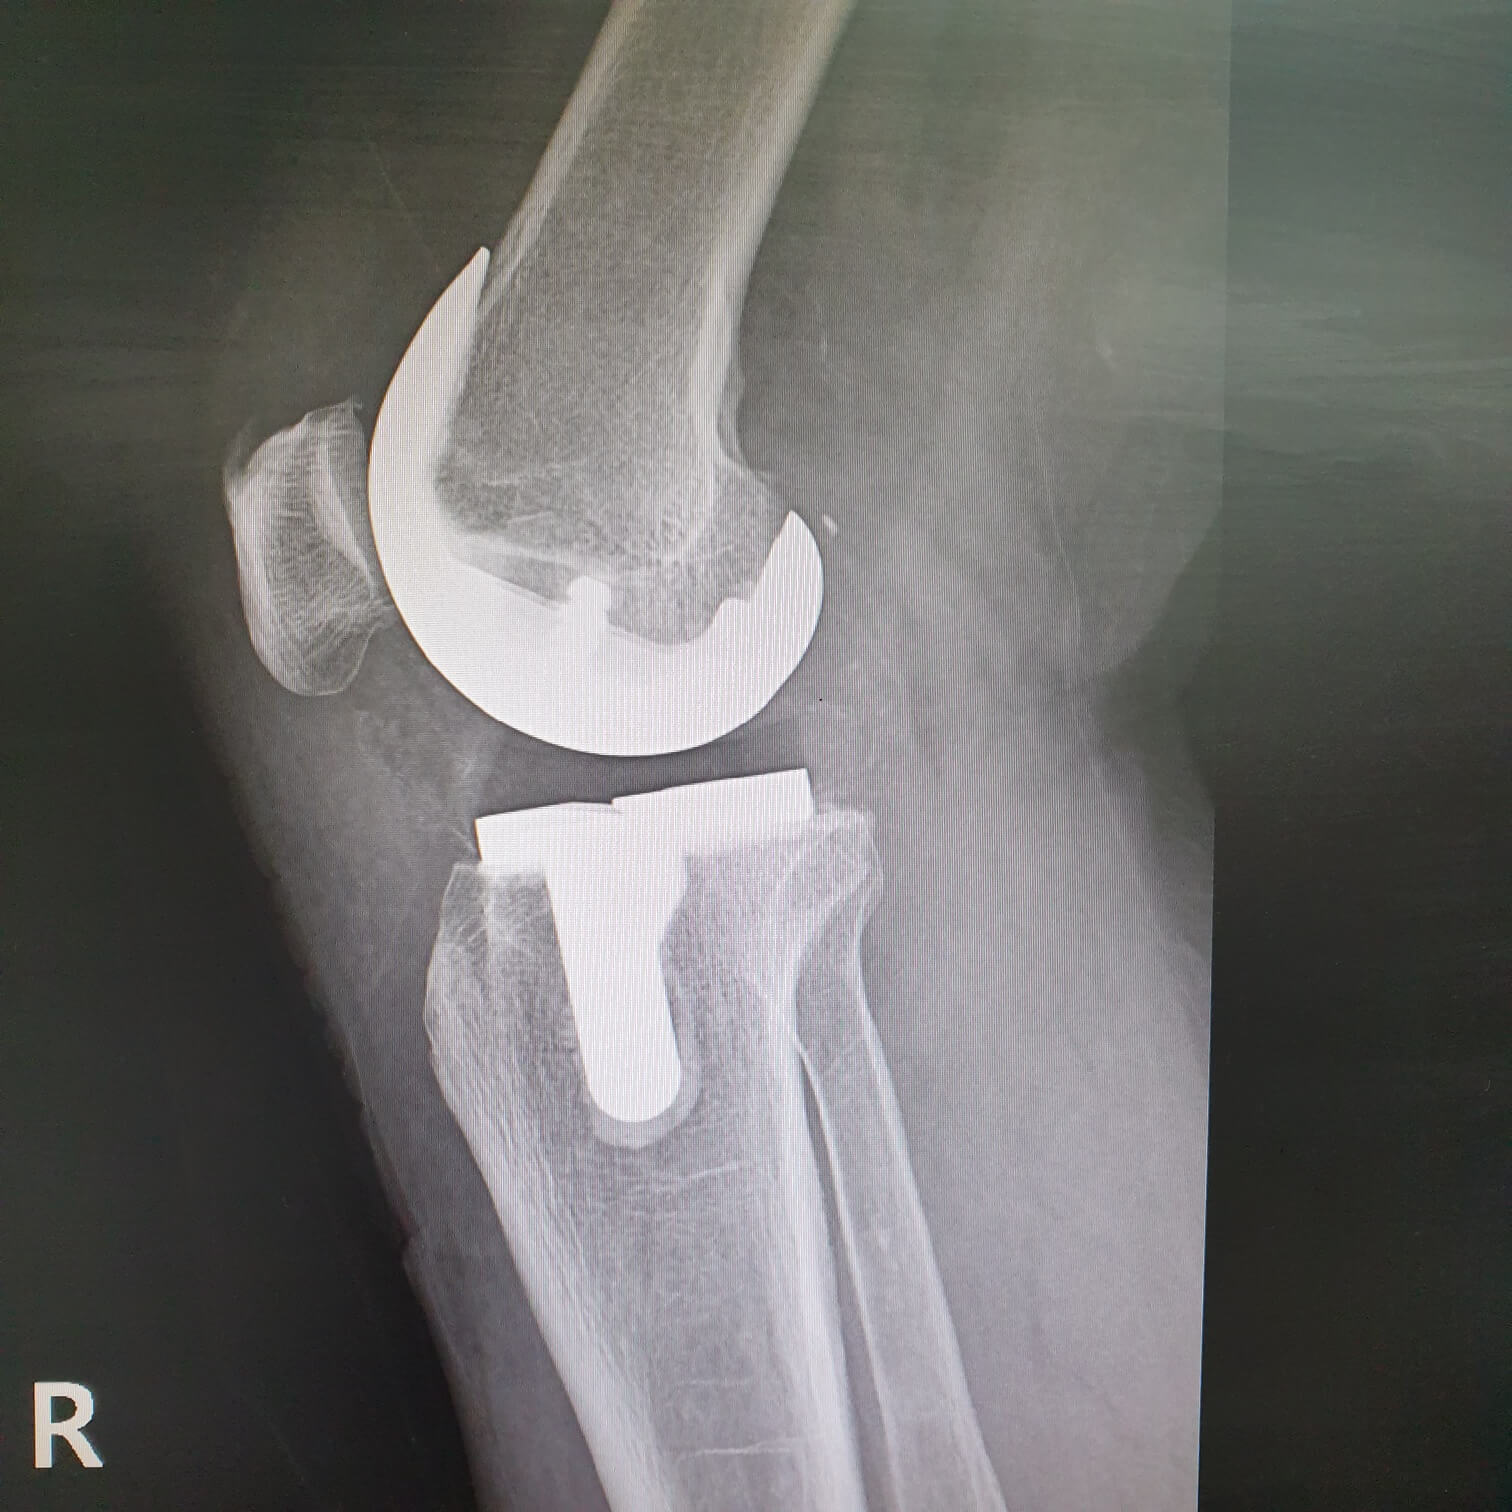

무릎의 퇴행성 관절염이나 류마티스 관절염으로 인해 관절이 파괴 된 경우 관절 연골과 뼈를 제거하고 관절 표면을 금속 삽입물과 고밀도 플라스틱으로 교체 삽입하는 수술을 말합니다.

가끔 무릎을 구부리거나 펴는 과정에서 삽입해 놓은 금속과 플라스틱이 부딪히는 소리가 날 수도 있으며 이러한 증상들은 대개의 경우 시간이 지나면서 없어지거나 감소됩니다.